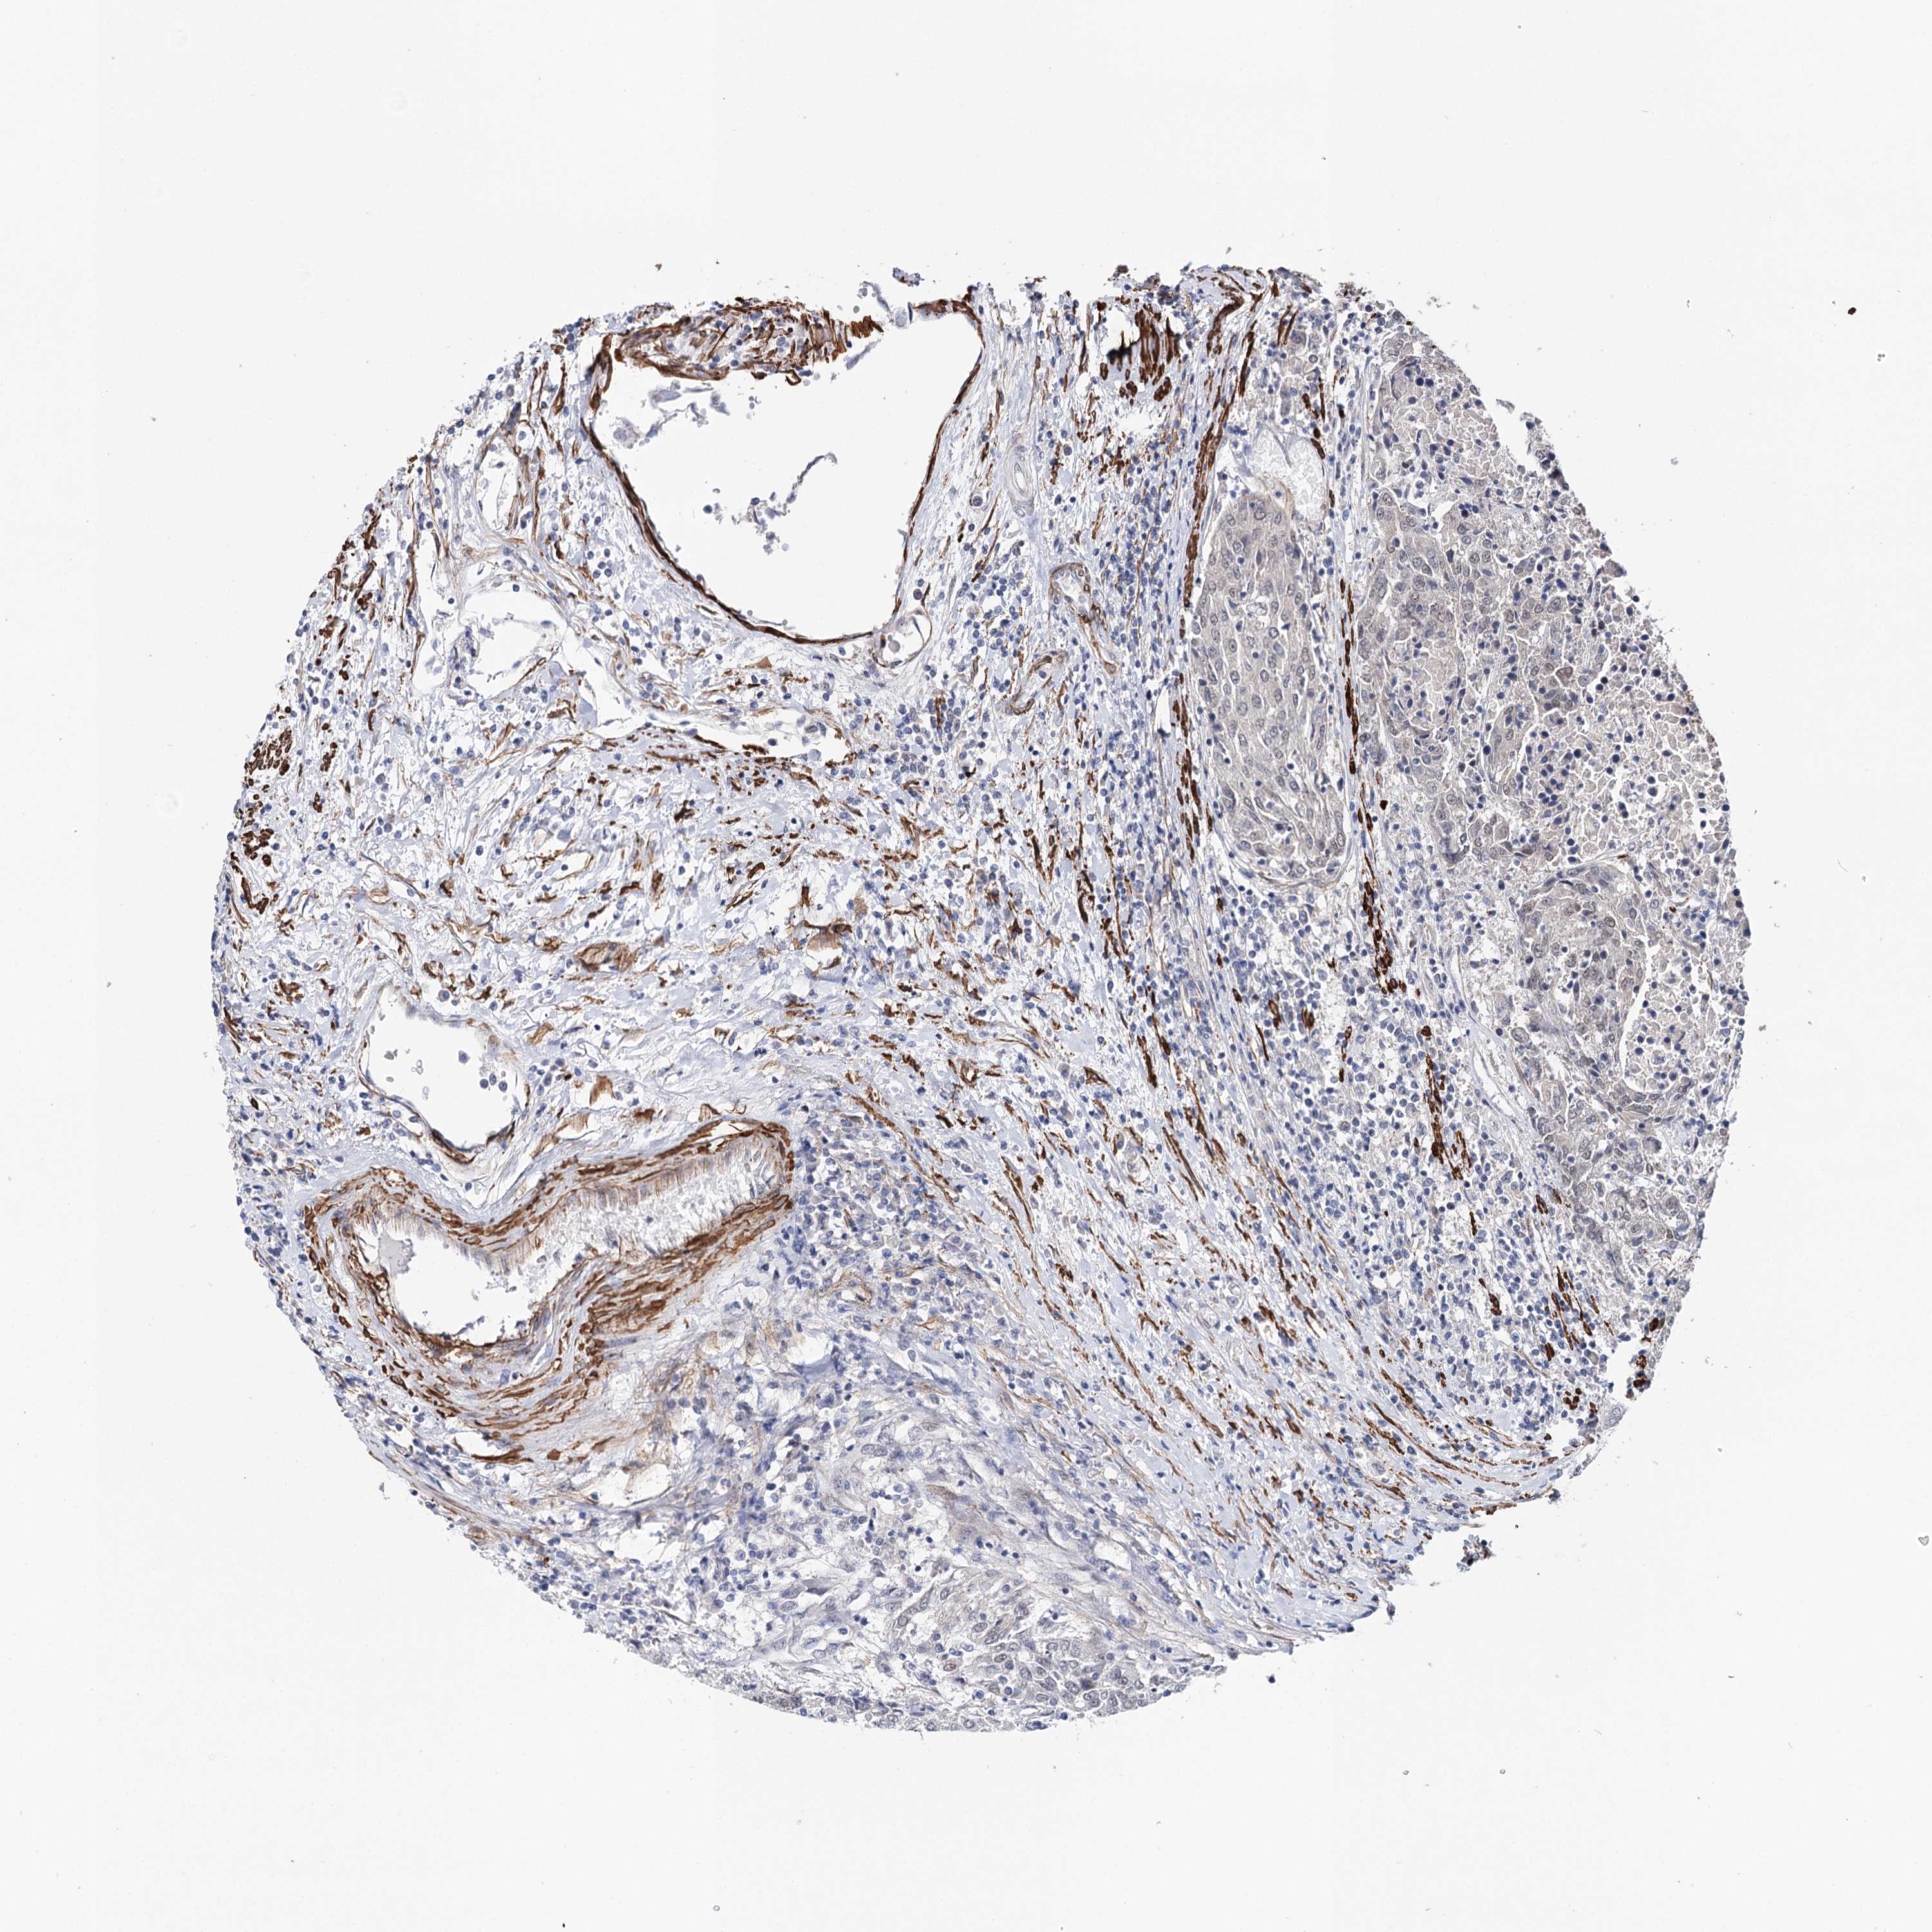

UROTHELIAL CANCER - Protein expressioni

A mouse-over function shows sample information and annotation data. Click on an image to view it in a full screen mode. Samples can be filtered based on level of antibody staining by selecting one or several of the following categories: high, medium, low and not detected. The assay and annotation is described here.

Note that samples used for immunohistochemistry by the Human Protein Atlas do not correspond to samples in the TCGA dataset.

Antibody stainingi

Antibody staining in the annotated cell types in the current human tissue is reported as not detected, low, medium, or high, based on conventional immunohistochemistry profiling in selected tissues. This score is based on the combination of the staining intensity and fraction of stained cells.

Each image is clickable and will lead to virtual microscopy that enables deeper exploration of all samples and also displays staining intensity scores, fraction scores and subcellular localization as well as patient and tissue information for each sample.

Antibody HPA037786

Antibody HPA038034

Antibody HPA038867

Antibody HPA038868

Urothelial carcinoma, High grade

Urothelial carcinoma, Low grade

Urothelial carcinoma, NOS